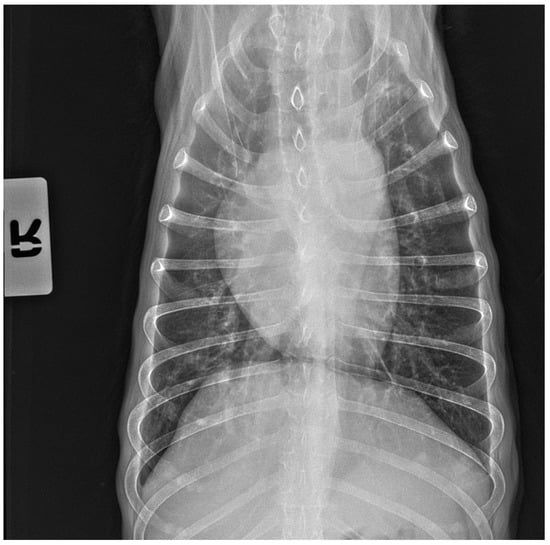

No pathological changes were detected in the lung parenchyma image in the X-ray (Figure 1 and Figure 2). The ultrasound examination revealed in all views a normal, aerated lung pattern. The pleural line was intact, and A-line artifacts were present (Figure 3). The sliding sign was also observed. Echocardiography revealed a mild thickening of the mitral valve leaflets and a slight regurgitation (Figure 4) of this valve. The size of the heart chambers was within the normal range, and myocardial contractility was normal.

Figure 2.

The thoracic X-ray image in the anteroposterior (AP) position shows no pathological alterations within the lung parenchyma and cardiac silhouette.